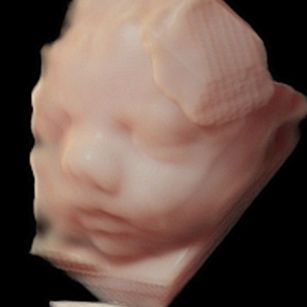

Skin: Becoming smoother as fat builds up underneath; baby is starting to look plumper and less wrinkly.

Muscles: Strengthening—movements are more coordinated and powerful.

Eyes: Baby can respond to light, open and close their eyes, and even start practicing blinking.